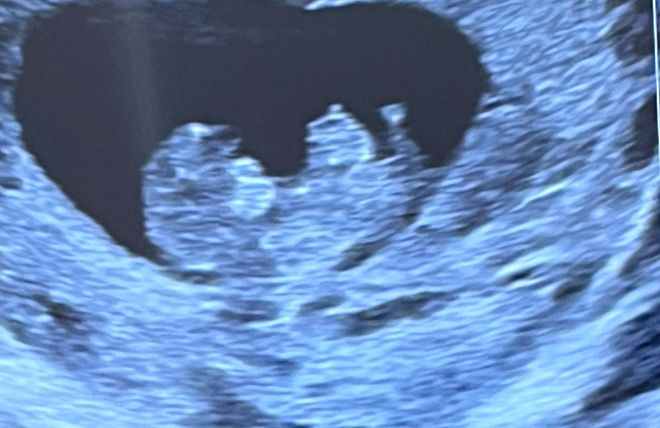

УЗИ 11 недель

Это может быть кишечник, до определенного времени он находятся вне брюшной полости, т.к. не хватает места. Потом эмбрион подрастает, и все встает на свои места. У нас на 10 неделе еще была, на 12 уже все "втянулось".Не обращайте внимания.

Склоняюсь к пуповине:) не переживайте:)

Может пуповина, а может помехи узи. Если врач не сказал ничего по этому поводу, то все в порядке ☺️